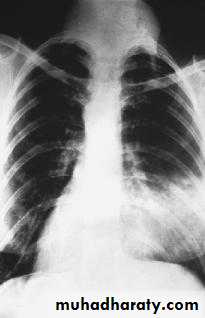

Chest x rayECG.

Pulmonary embolism.

Pneumonia.